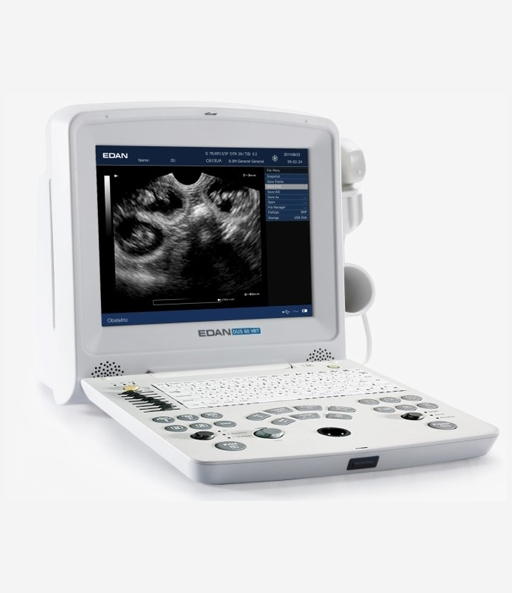

DUS60 VET

Veterinary Digital Ultrasonic Diagnostic Imaging System

U50 VET

Prime Diagnostic Ultrasound System

U60 VET

Veterinary Diagnostic Ultrasound System

EDAN-Acclarix AX3 VET

Diagnostic Ultrasound System

U2 VET

Veterinary Diagnostic Ultrasound System

Acclarix LX3 VET

Veterinary Diagnostic Ultrasound System

Acclarix AX9 VET

Veterinary Diagnostic Ultrasound System